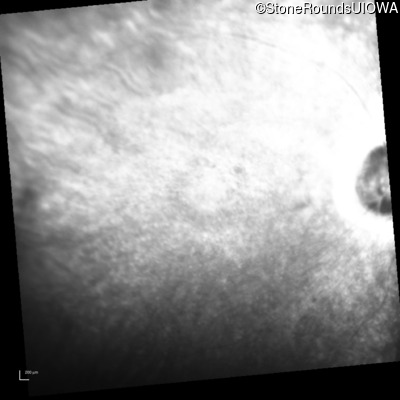

Infrared Fundus Photograph - Right - 20/50

Exemplar